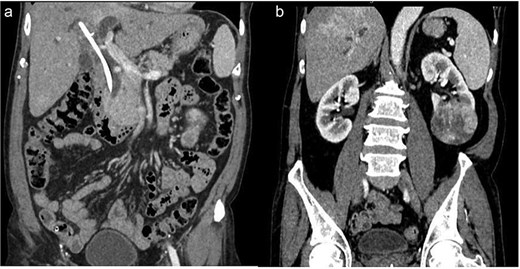

Examination revealed mild right upper quadrant tenderness and lump in left lumbar region. Liver function tests showed mildly elevated transaminases. Ultrasonography and contrast-enhanced computed tomography showed a necrotic lesion in the left kidney (6.5 × 5.4 cm), consistent with RCC (Fig. 1a), along with a retained CBD stent with biliary sludge, and dilated biliary ducts (Fig. 1b).

(a) Retained CBD stent. (b) Necrotic mass at lower pole of left kidney.